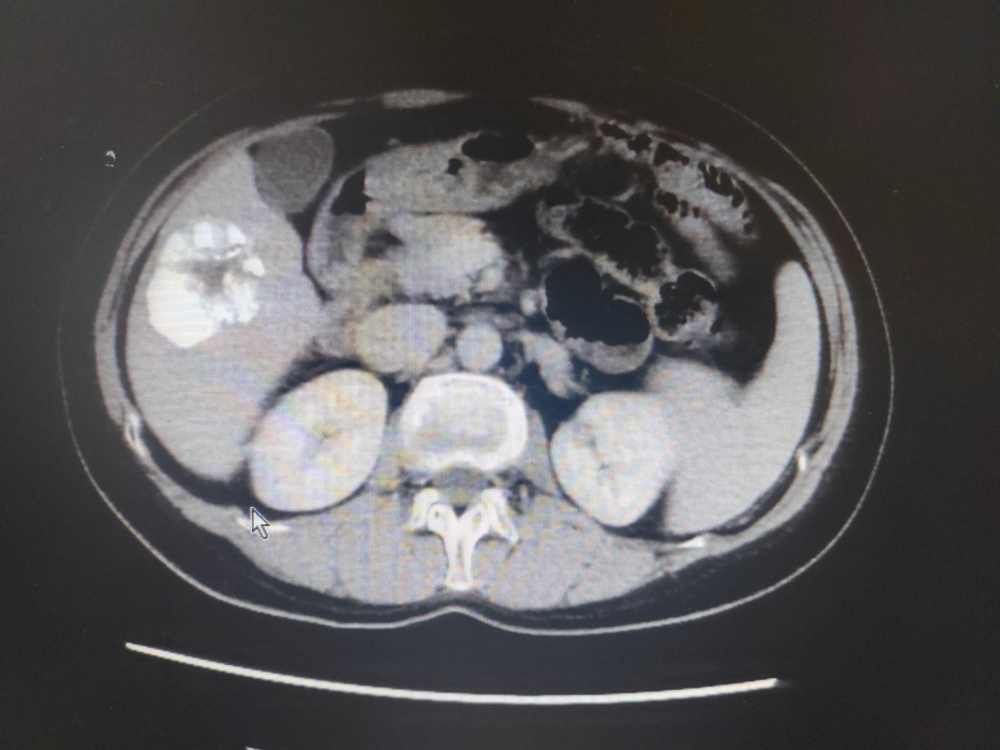

患者劉某,男,47歲,因腹痛於2022年1月17日在我院門診就(jiù)診,門診CT示:1、慢(màn)支肺氣腫及慢性炎症;2、右上(shàng)肺小結節,建議3-6個月(yuè)複查,3、掃及髒內異常密度灶建議必要時進一步檢查。當即轉往江西省腫瘤醫院就診,完善檢查,診斷為原發性肝癌,當時予以TACE術及卡瑞利珠單抗聯合多納菲尼靶向治療。2022年3月6日為行免疫治療前往我院內三(sān)科住院治療,完善檢查示:上腹部增強CT示:肝VI段及V段腫塊並碘(diǎn)油沉(chén)積,係介入治療術後改變,肝V段病(bìng)灶大部分存活,肝VI段病灶小(xiǎo)部分存活:肝I1 段小結節並(bìng)異常強化考慮小血管瘤:肝內多發(fā)微囊(náng)腫,肝門及腹(fù)膜後多(duō)發稍大(dà)淋巴結。甲胎蛋白(bái)異質體:322.82ng/ml個甲胎蛋白(bái):818.02ng/ml個甲胎蛋白異質體比率:40.09%完善術前檢查於2022 年3月10日在南昌(chāng)大學(xué)第(dì)一附屬(shǔ)醫院羅榮光副主任醫師指導下,內(nèi)三(sān)科肖緒銀副(fù)主任醫師、柯於鋒副主任醫師、盧軍主治醫師(shī)完成了我院首例經導管(guǎn)肝癌栓塞術,術後恢複良好,此後(hòu)患者定期行免(miǎn)疫治療。此後定期複查病情穩(wěn)定,2023年4月15日(rì)CT示:與2022年10月25日上腹部CT平掃(sǎo)及增(zēng)強比(bǐ)較:1、肝VI段及V段腫塊並碘油沉積,係介(jiè)入治療術後改變,腫塊大致相仿,未見明確強化,隨診(zhěn)複查(chá)。2、肝段小(xiǎo)結節(jiē)並異常強化,考慮小血管瘤肝內多發微囊腫:肝門及腹膜(mó)後多發稍大淋巴結;均較前片變化不(bú)著。3、脾前緣無明顯強化低密度灶,同前。4、右腎(shèn)微小結石。2023年4月16日(rì)甲(jiǎ)胎蛋(dàn)白:9.39ng/ml1療效評價大PR。

2023年4月15日上腹部增強CT